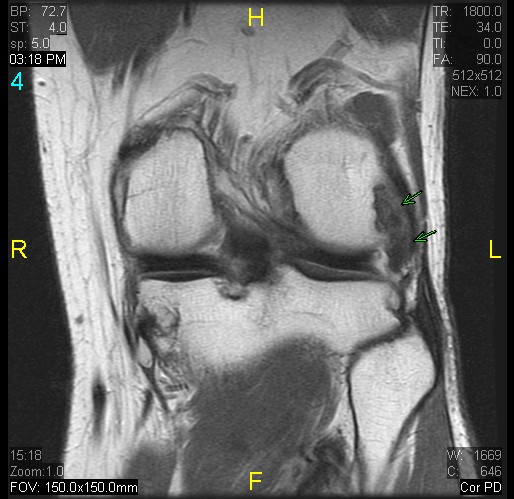

Discussion

Presumed gout in the knee

Diagnosis

gout arthritis ( RID3567 )